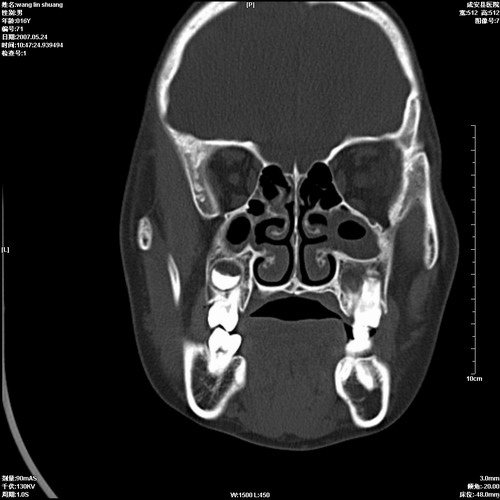

病人,男 16岁,鼻旁右肿胀,其余无不适感,ct图片

1、典型右侧根尖囊肿。

2、双侧上颌窦、筛窦、蝶窦炎

1\\左侧上颌骨含牙囊肿

2\\两上颌窦炎

右侧上颌骨含牙囊肿.双侧上颌窦炎症.

右侧上颌骨含牙囊肿.双侧上颌窦、蝶窦右侧炎症.

1、左侧上颌骨含牙囊肿。

典型的右侧上颌骨含牙囊肿,双侧上颌窦、右侧蝶窦炎症。